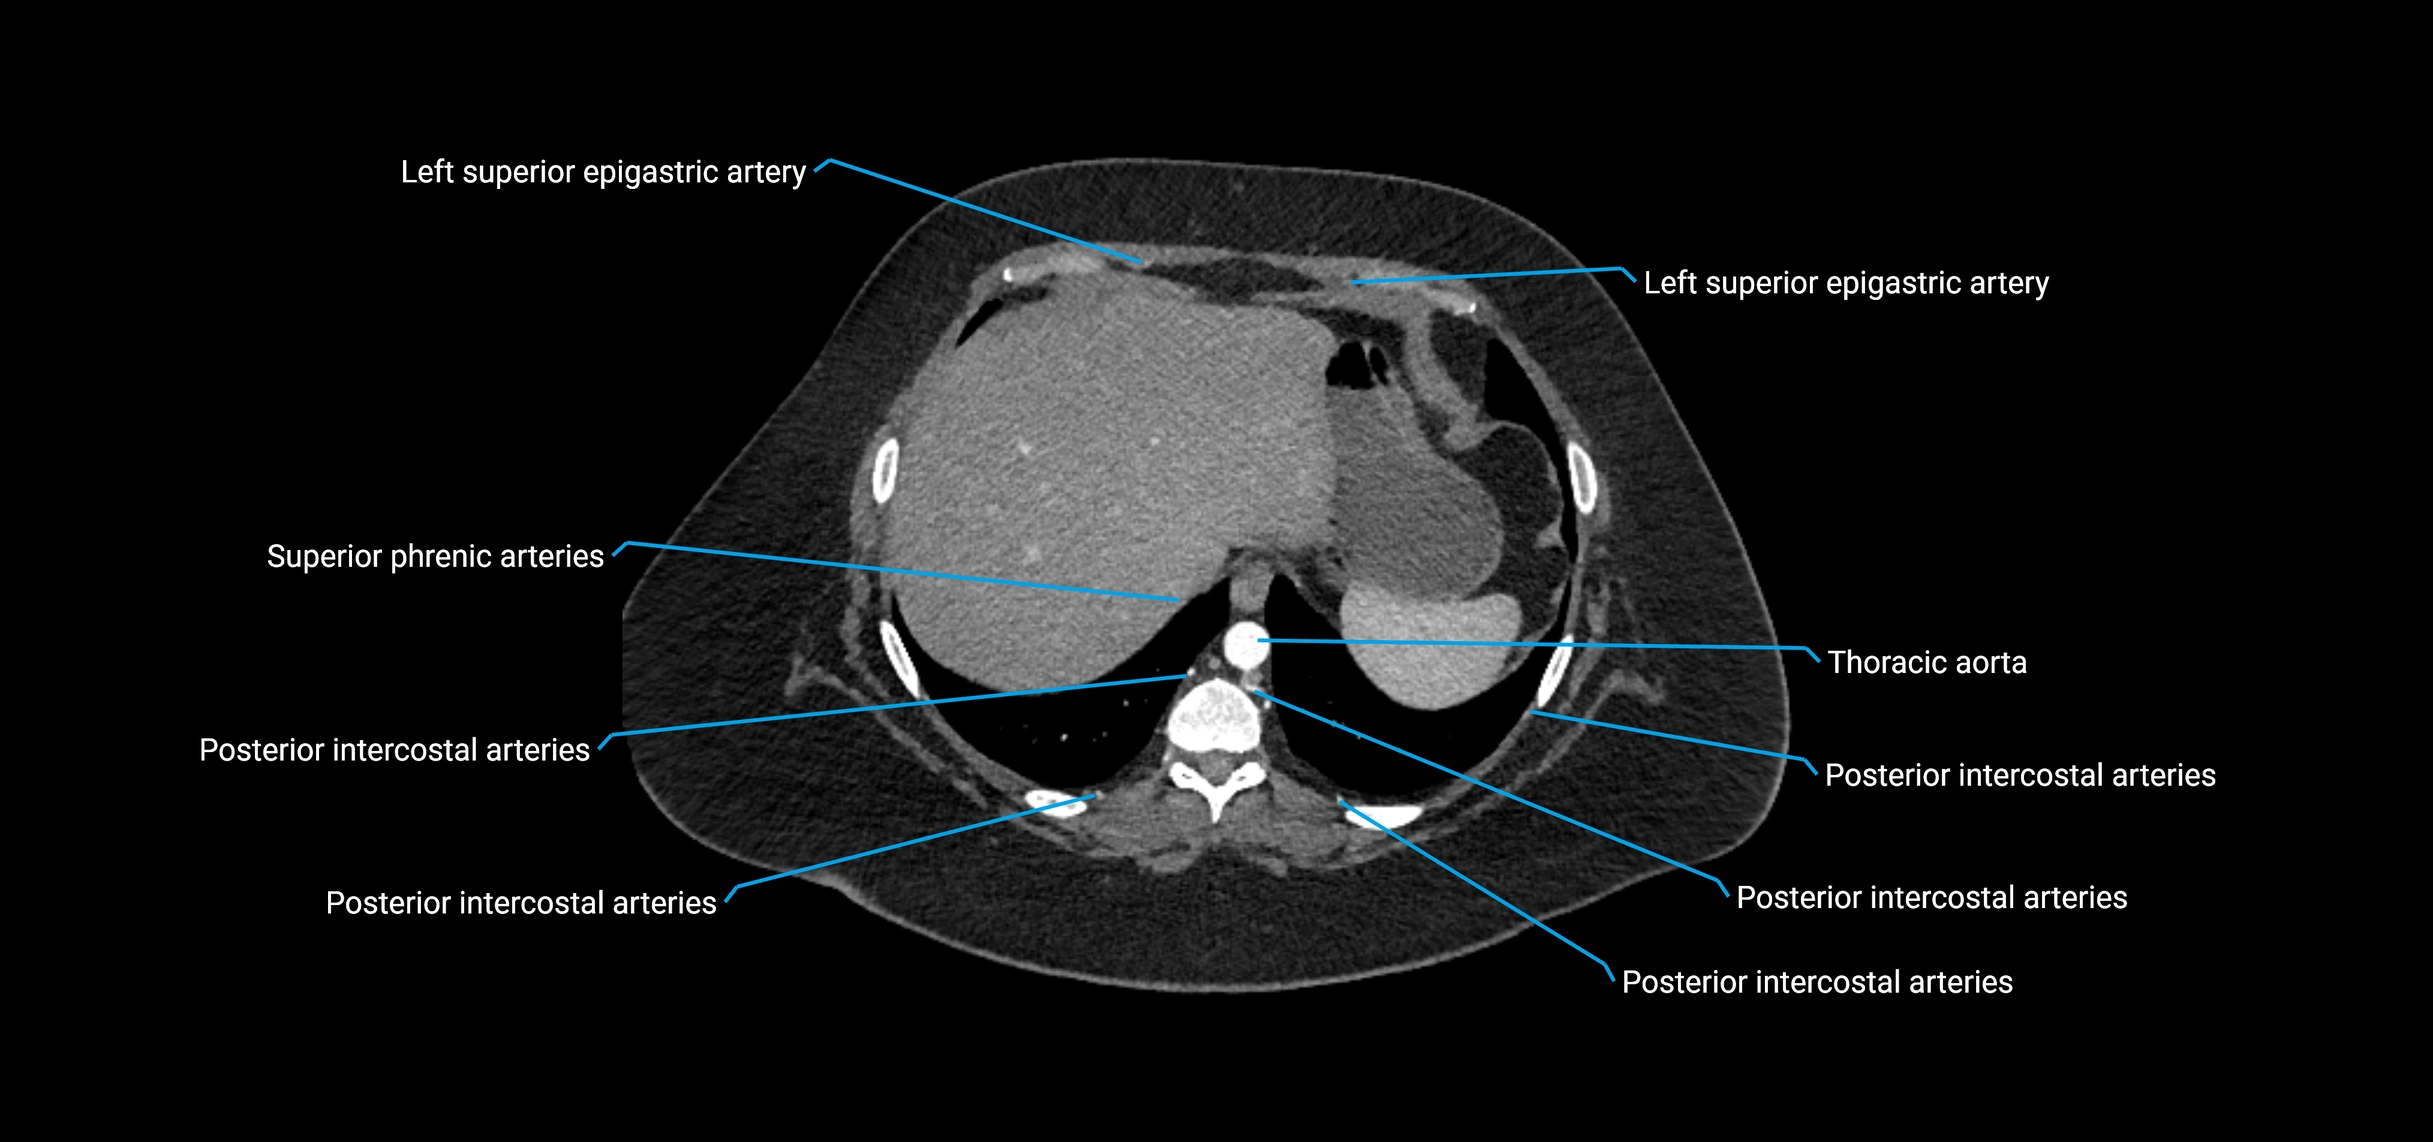

CT Appearance

Non-contrast CT:

• Appears as a tubular soft tissue structure anterior to vertebral bodies

• Calcified atherosclerotic plaques appear as hyperdense foci along the wall

• Useful for screening abdominal aortic aneurysm (AAA) size and mural calcification

Contrast-enhanced CT (CTA):

• Gold standard for abdominal aortic imaging

• Provides excellent detail of lumen, wall, aneurysm, thrombus, and branch vessels

• Multiplanar and 3D reconstructions help in aneurysm measurement, stent graft planning, and dissection evaluation

• Detects acute rupture, traumatic injury, or occlusion with high sensitivity

CT images

image